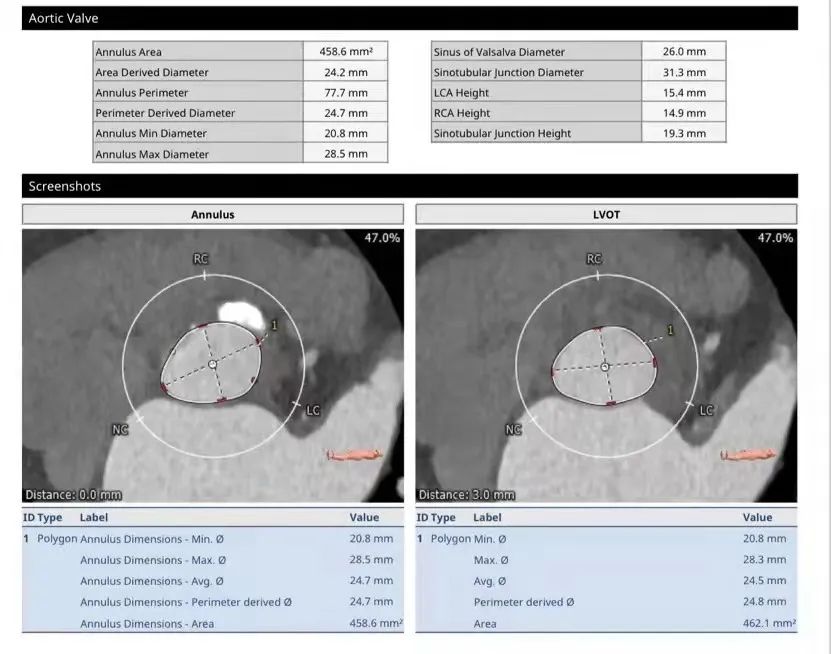

TYPE0型二叶式主动脉瓣,瓣叶严重钙化增厚。冠脉无明显狭窄,冠脉开口高度左侧15.4mm、右侧14.9mm,冠状窦水平无瓣叶,TAVR手术冠脉闭塞风险低。升主动脉扩张,主动脉扭曲。双侧股动脉通畅,无明显钙化。

瓣膜选择:基于术前CTA的测量结果,因二叶瓣严重钙化为降低瓣环破裂等风险选择偏小一号的人工瓣膜(downsize策略)植入23 mm SAPIEN 3瓣膜。